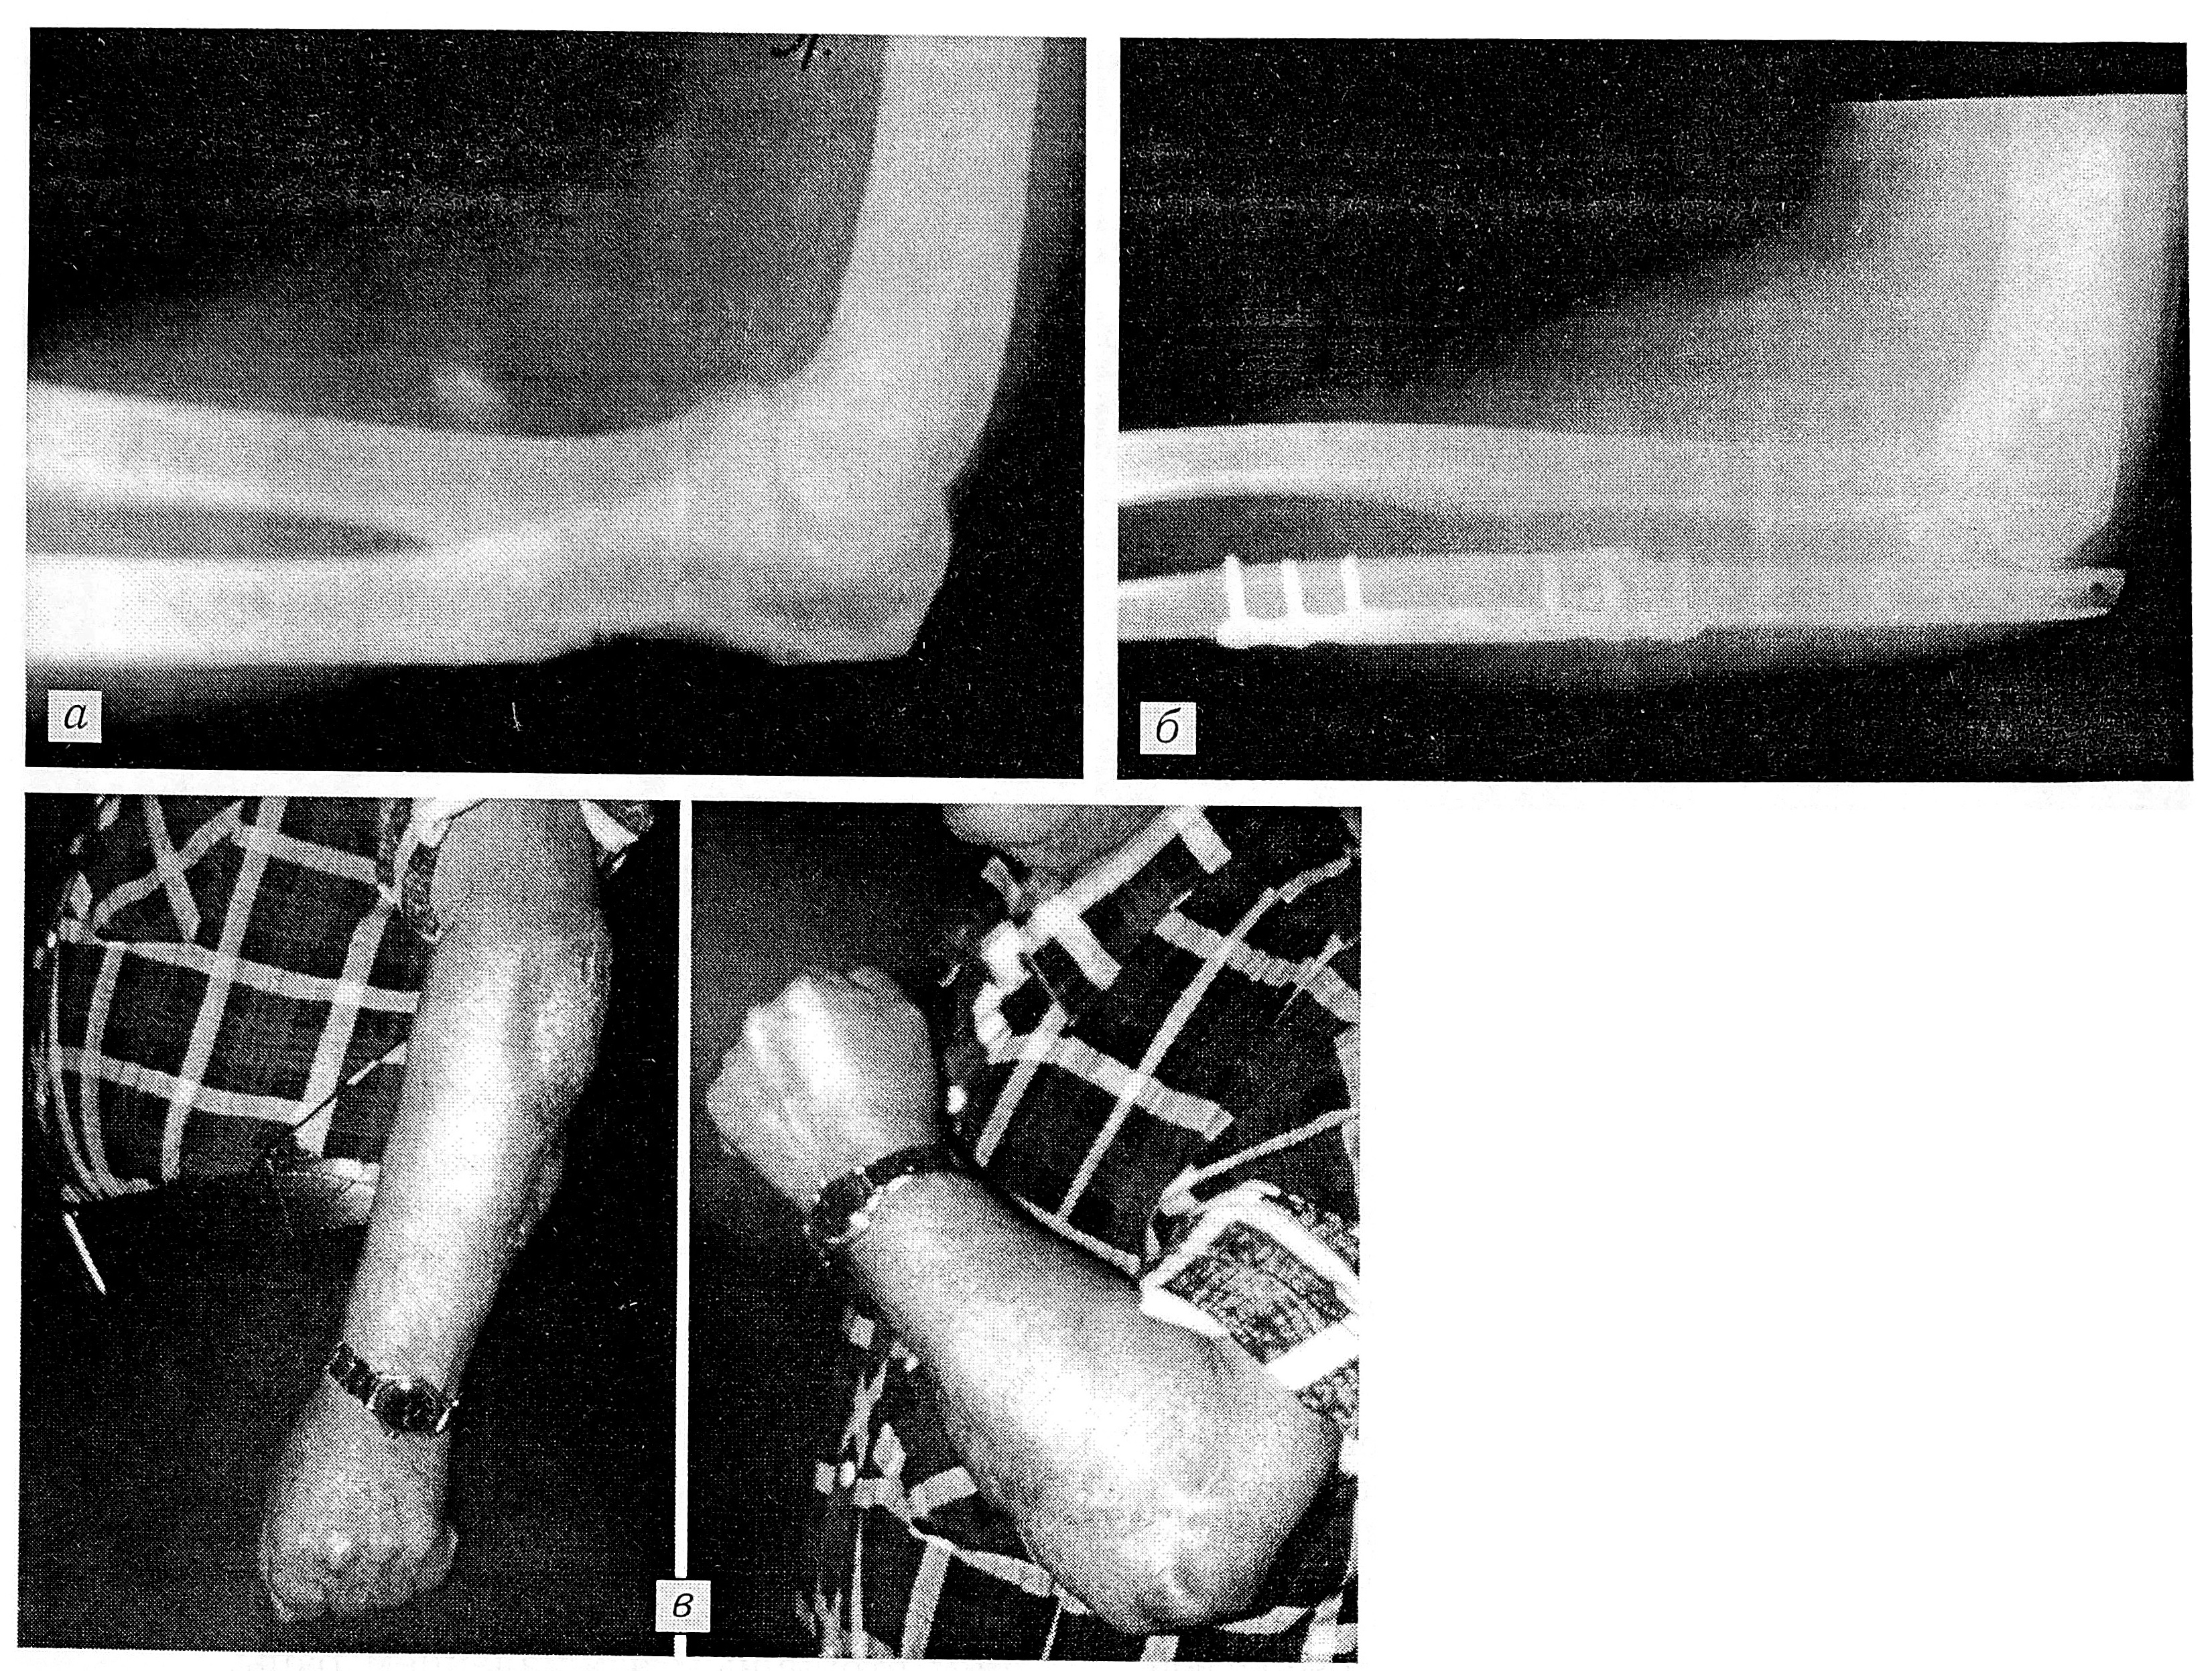

Больной М-н, 65 лет, поступил с диагнозом: рабдомиосаркома мягких тканей левого предплечья. В 1986 г. была проведена дистанционная гамма-терапия с последующим иссечением опухоли. В 1987 и 1989 гг. — повторные иссечения по поводу рецидивов опухоли (в комбинации с гамма- терапией в 1989 г.). В марте 1991 г. — очередной рецидив опухоли с прорастанием в локтевую кость (рис. 3, а). Проведена химиотерапия (платидиам и фармарубицин), не давшая эффекта.

23.04.91 выполнена резекция проксимальной трети локтевой кости единым блоком с опухолью и окружающими мягкими тканями; образовавшийся дефект замещен костно-мышечным лоскутом из фрагмента малоберцовой кости вместе с малоберцовыми мышцами, пересаженным на микрососудистых анастомозах. Остеосинтез пластиной (рис. 3, б). Малоберцовые мышцы использовались для закрытия мягкотканного дефекта и восстановления целости трехглавой мышцы. Поверхность лоскута укрыта свободным кожным трансплантатом. Гистологическое исследование: рабдомиосаркома, разрушающая кость. Послеоперационный период без осложнений. Через 2 года прогрессирования заболевания нет. Несмотря на значительное повреждение локтевого сустава, образование после удаления опухоли обширного костного дефекта и дефекта окружающих мягких тканей, активные и пассивные движения в локтевом суставе сохранены в полном объеме (рис. 3, в).

Рис. 3. Больной М-н. Рабдомиосаркома мягких тканей левого предплечья с разрушением локтевой кости. а — рентгенограмма левого локтевого сустава до операции, б — через 3 мес после операции; в — функция локтевого сустава через 6 мес после операции.